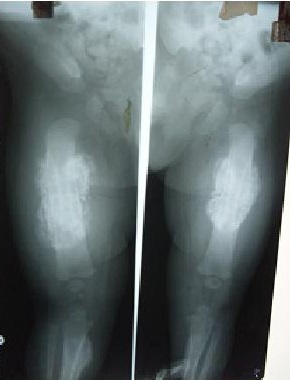

A 4 month old male child presented with fever, excessive crying and swelling of the face. Plain radiographs were done as shown above.

What is the diagnosis?

Caffey disease or Infantile cortical hyperostosis is a benign, rare, proliferating bone disease affecting infants {1}. Classically, Caffey disease occurs in the first year of life { Less than 5 months}. It is characterized by clinical triad of fever, soft tissue swelling and hyperirritability and a clinching radiograph picture of underlying cortical hyperostosis {2}. Although the etiology of caffey disease remains unclear, many clinical and pathologic features are suggestive of inflammatory process {3}. All races are affected, seen equally in boys and girls {1}. Laboratory investigation may show an elevated ESR, an elevated serum alkaline phosphatase, moderate leukocytosis, thrombocytosis and anemia {4}. Clinical course of caffey disease is highly variable, ranging from self limited to protracted illness. Clinical differential diagnosis includes Osteomyelitis, Parotitis and parotid gland abscess and bone tumors of the affected area. Management is essentially palliative aimed at pain relief but some authors claim a good response to high dose immunoglobulin {5}. Corticosteroids have been used to hasten bone remodeling and Indomethacin has been used to control flare ups.